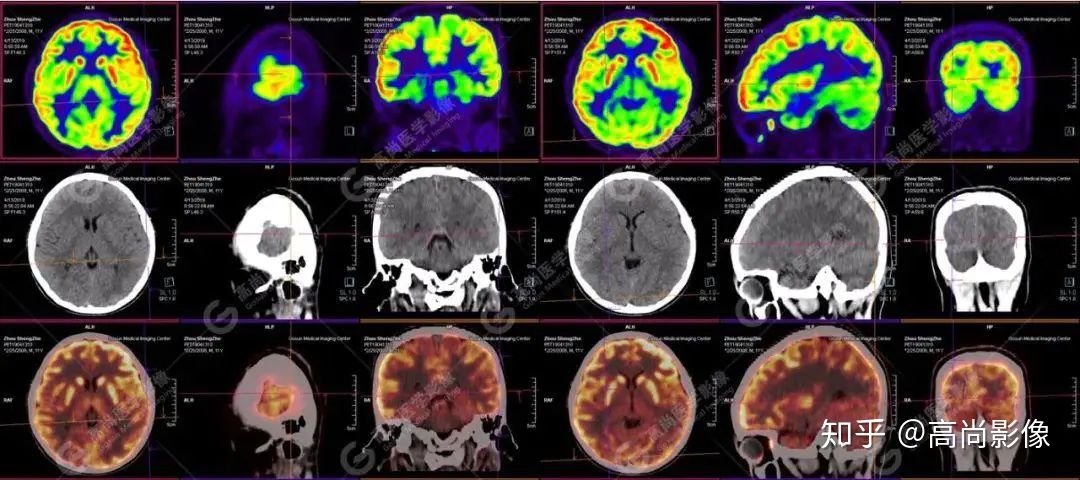

【PET/CT 】

提示: 大腦左側(cè)頂葉、顳葉(上部)及右側(cè)額葉、枕葉、顳葉(下部)腦皮質(zhì)代謝廣泛減低,尤以右枕葉為著,多考慮與癲癇發(fā)作相關(guān)。